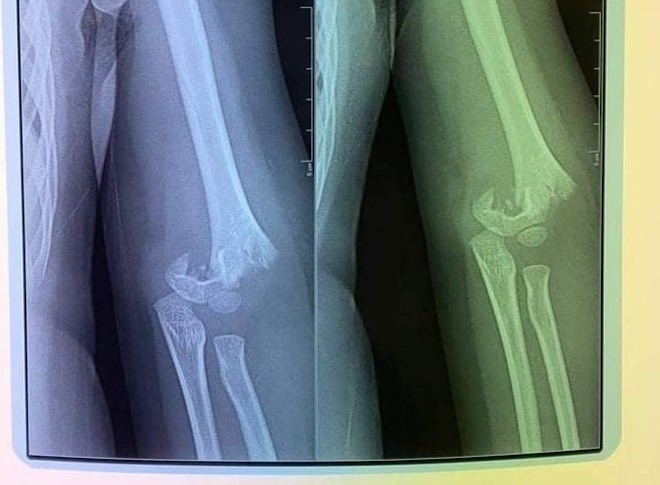

Hình ảnh chụp phim cho thấy trẻ bị gãy xương cánh tay. (Ảnh: Gia đình cung cấp)

Theo phản ánh của chị N.T.T.H - phụ huynh cháu N.B.T, 5 tuổi, học tại trường Mầm non Vườn trẻ thơ - Kid's Garden (địa chỉ tại tầng 1, nhà A3 chung cư số 250 Minh Khai, quận Hai Bà Trưng), ngày 15/9 trong giờ học ngoài trời, giáo viên của trường để các cháu chơi tự do, dẫn đến 1 bạn đẩy ngã con chị từ cầu trượt văng ra ngoài. Con chị bị gãy khuỷu tay, phải mổ cấp cứu.

Hiện N.B.T đã về nhà điều trị với lịch hẹn phẫu thuật lần 2 sau 4 tuần. Trong khi đó, theo phụ huynh, suốt thời gian qua, nhà trường không thành thật nhận trách nhiệm khiến gia đình chị bức xúc.